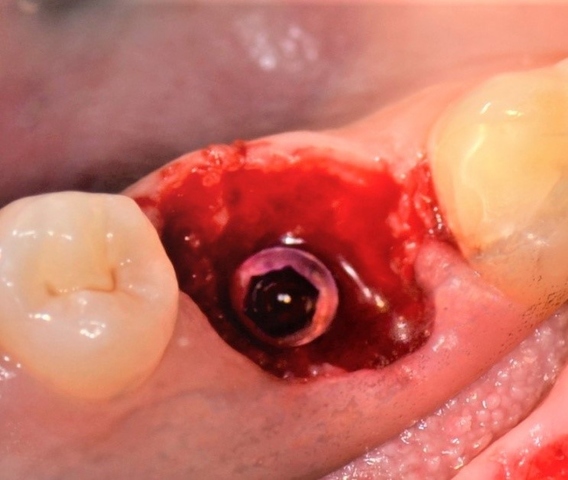

Diagnostykę poszerzono o badanie tomografii wiązki stożkowej (ryc. 4-6). Region implantacji zwymiarowano w trzech płaszczyznach w specjalnym programie komputerowym 3Shape Implant Studio® (3Shape, Kopenhaga, Dania), wykonano szablon implantologiczny i przystąpiono do procedury chirurgicznej. Zaprojektowano użycie wszczepu o wymiarach 4,2 x 10 mm.

Ryc. 4. Przekrój zęba 36 w płaszczyźnie czołowej. Ryc. 5. Przekrój zęba 36 w płaszczyźnie strzałkowej.

Ryc. 6. Przekrój zęba 36 w płaszczyźnie horyzontalnej.